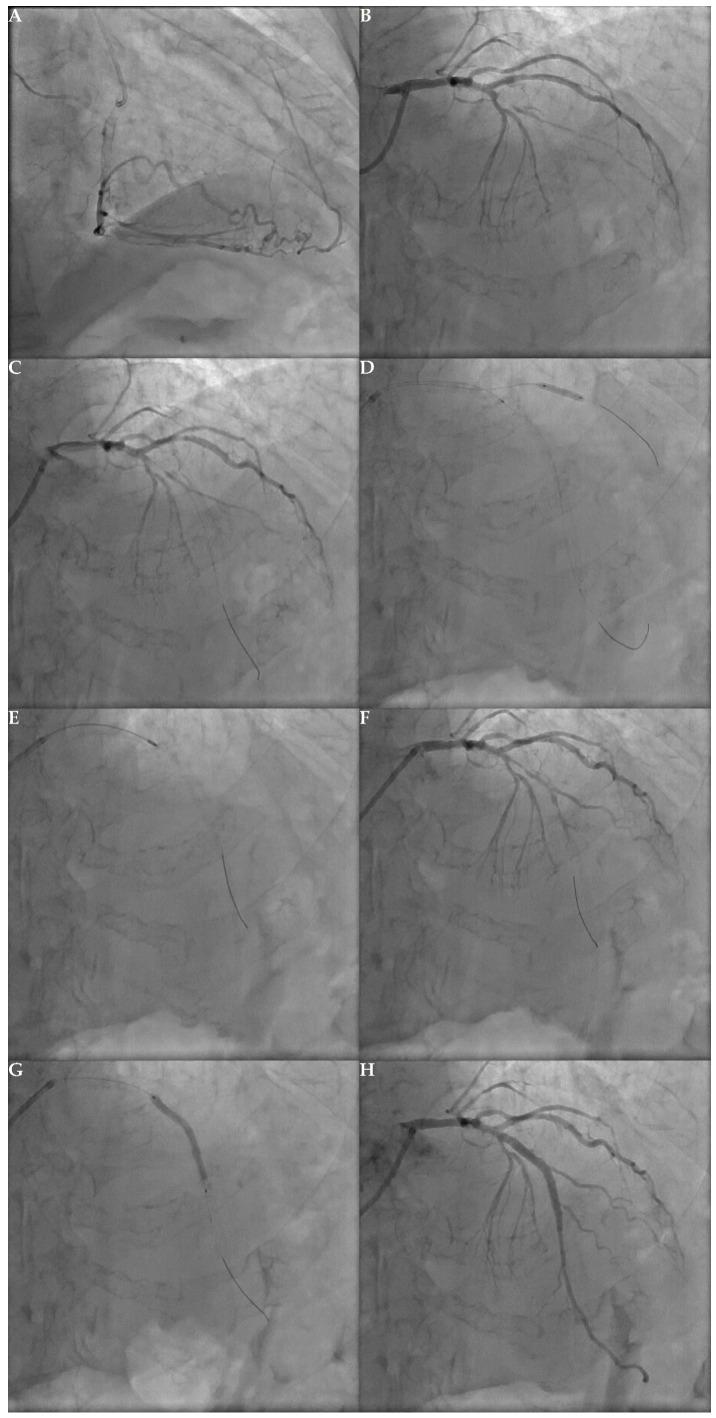

In the aging society, the issue of coronary chronic total occlusion (CTO) has become a challenge for invasive cardiologists. Despite the lack of clear indications in European and American guidelines, the rates of percutaneous coronary interventions (PCI) for CTO increased over the last years. Well-conducted randomized clinical trials (RCT) and large observational studies brought significant and substantial progress in many CTO blind spots. However, the results regarding the rationale behind revascularization and the long-term benefit of CTO are inconclusive. Knowing the uncertainties regarding PCI CTO, our work sought to sum up and provide a comprehensive review of the latest evidence on percutaneous recanalization of coronary artery chronic total occlusion.

在老龄化社会中,冠状动脉慢性完全闭塞(CTO)问题已成为侵入性心脏病专家面临的一项挑战。尽管欧美指南中缺乏明确的适应症,但近年来CTO的经皮冠状动脉介入治疗(PCI)率仍有所上升。精心开展的随机临床试验(RCT)和大型观察性研究在许多CTO盲点方面取得了重大实质性进展。然而,关于血运重建背后的原理以及CTO的长期获益的结果尚无定论。鉴于PCI治疗CTO存在不确定性,我们的工作旨在总结并全面回顾冠状动脉慢性完全闭塞经皮再通的最新证据。